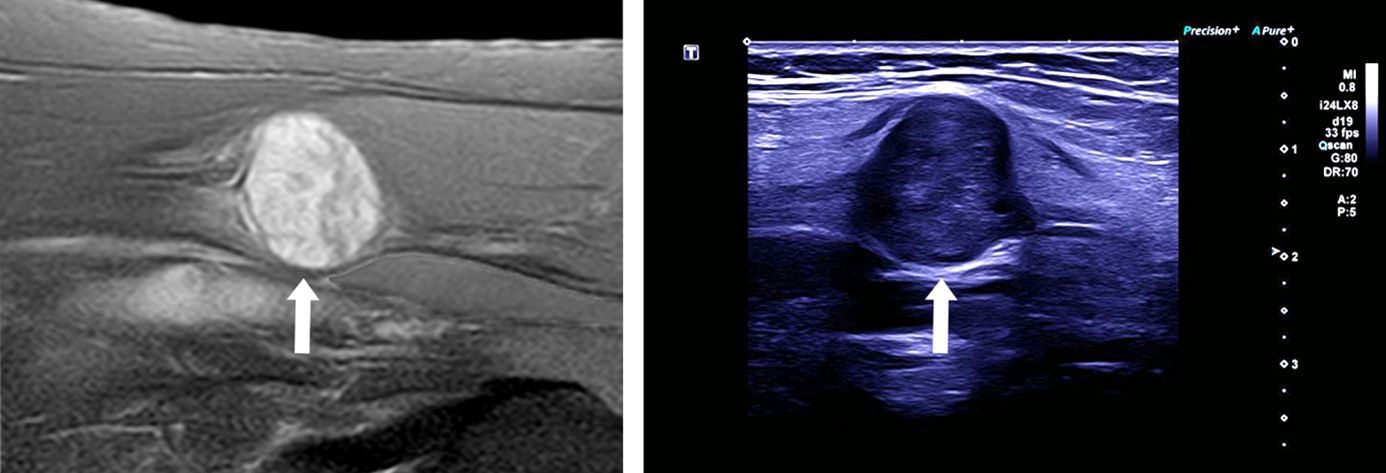

Entscheidend zur Diagnostik tragen kernspintomographische Aufnahmen (MRT) der betroffenen Körperregion bei. Auch hochauflösende Ultraschalluntersuchungen können hilfreich sein, um eine Beurteilung und Festlegung der Therapiestrategie zu ermöglichen.

Die neuralgische Amyotrophie ist eine entzündliche Erkrankung, welche sich typischerweise durch plötzlich auftretende Schmerzen (häufig im Bereich der Schulter oder des Arms), gefolgt von einer Lähmung der Muskulatur, äußert. Eine Ursache ist nicht immer sofort erkennbar. Während die Schmerzen mit der Zeit abklingen, können die Lähmungen anhalten und infolge der Entzündungsreaktion narbige Einschnürungen an den betroffenen Nerven entstehen. Die Erkennung dieser Einschnürungen („Konstriktionen“) kann zunächst schwierig sein und erfordert spezielle Untersuchungsmethoden im Sinne einer hochauflösenden Neurosonographie durch erfahrene Neurolog*innen oder einer MR-Neurographie. Sollten sich solche Nervenkonstriktionen bestätigen kann eine operative Therapie gute Ergebnisse erzielen.

Ein lange Zeit weitgehend unbekanntes und weiterhin unterdiagnostiziertes Krankheitsbild stellt die neuralgische Amyotrophie, früher auch Plexusneuritis oder Schulteramyotrophie, dar. Hierbei handelt es sich um eine entzündliche Nervenerkrankung, deren Ursache nicht immer geklärt werden kann. Risikofaktoren stellen eine übermäßige mechanische Beanspruchung (z.B. durch ungewohnte starke körperliche Aktivität), immunologische Auslöser (z.B. Infektionen) oder eine genetische Veranlagung dar. Durch Verbesserungen in der Diagnostik, insbesondere dem hochauflösenden Nervenultraschall sowie der Magnetresonanzneurographie gelingt eine zunehmend bessere bildgebende Darstellung des gesamten Verlaufs peripherer Nerven. Dabei können einerseits entzündlich bedingte Schwellungen der Nerven festgestellt und die Diagnose bestätigt werden.

Die neurologische Akutbehandlung besteht aus schmerzstillenden Mitteln sowie hochdosierten entzündungshemmenden Cortison-Infusionen mit. Häufig bilden sich die Beschwerden darunter nach einigen Wochen wieder zurück. Immer wieder kommt es jedoch zu einem Fortbestehen der Lähmungen. Mithilfe der oben genannten Fortschritte bei bildgebenden Untersuchungen zeigte sich in den letzten Jahren, dass bei diesen Patientinnen und Patienten häufig narbige Einschnürungen der betroffenen Nerven bestehen, (sogenannte uhrglasförmige Nervenkonstriktionen), die den Nerv sogar verdreht erscheinen lassen können („Torsionen“). Bei Vorhandensein solcher Konstriktionen ist in der Regel eine medikamentöse Behandlung nicht weiter erfolgversprechend. Durch eine operative Narbenlösung kann dann in der Regel eine gute Erholung der Nervenfunktionen erreicht werden.